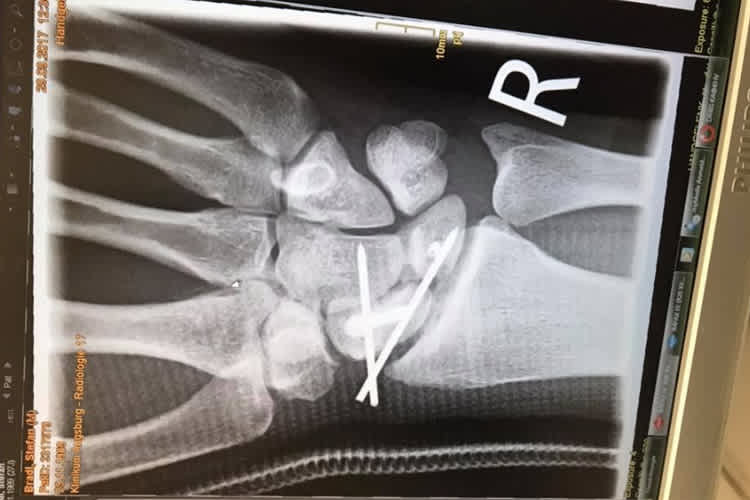

Bradl wurde in einem gut zweistündigen Eingriff von Dr. Stefan Krischak im Klinikum Augsburg die rechte Hand gerichtet. Das Mondbein und das Kahnbein waren um mehr als drei Millimeter auseinander gedriftet, das skapholunäre Band, welches die beiden Knochen verbindet, war beschädigt. "Ich bekam einen Draht eingesetzt mit einem Haken", erzählte Bradl SPEEDWEEK.com. "Der Haken ist am Mondbein befestigt, er wird dafür sorgen, dass das Band heilt und alles so zusammen kommt, wie es zusammen gehört. Leider ist der Heilungsverlauf sehr langwierig." Mitte November muss der Bayer erneut unters Messer, dann wird der Draht aus der Hand entfernt. Frühestens zwei Wochen nach der OP ist Bradl wieder einsatzfähig. Wie es 2018 weitergeht, weiß der Moto2-Weltmeister von 2011 nicht. "Wenn das mit Red Bull Honda nicht klappt, habe ich einen Plan B und C", versichert der 27-Jährige.